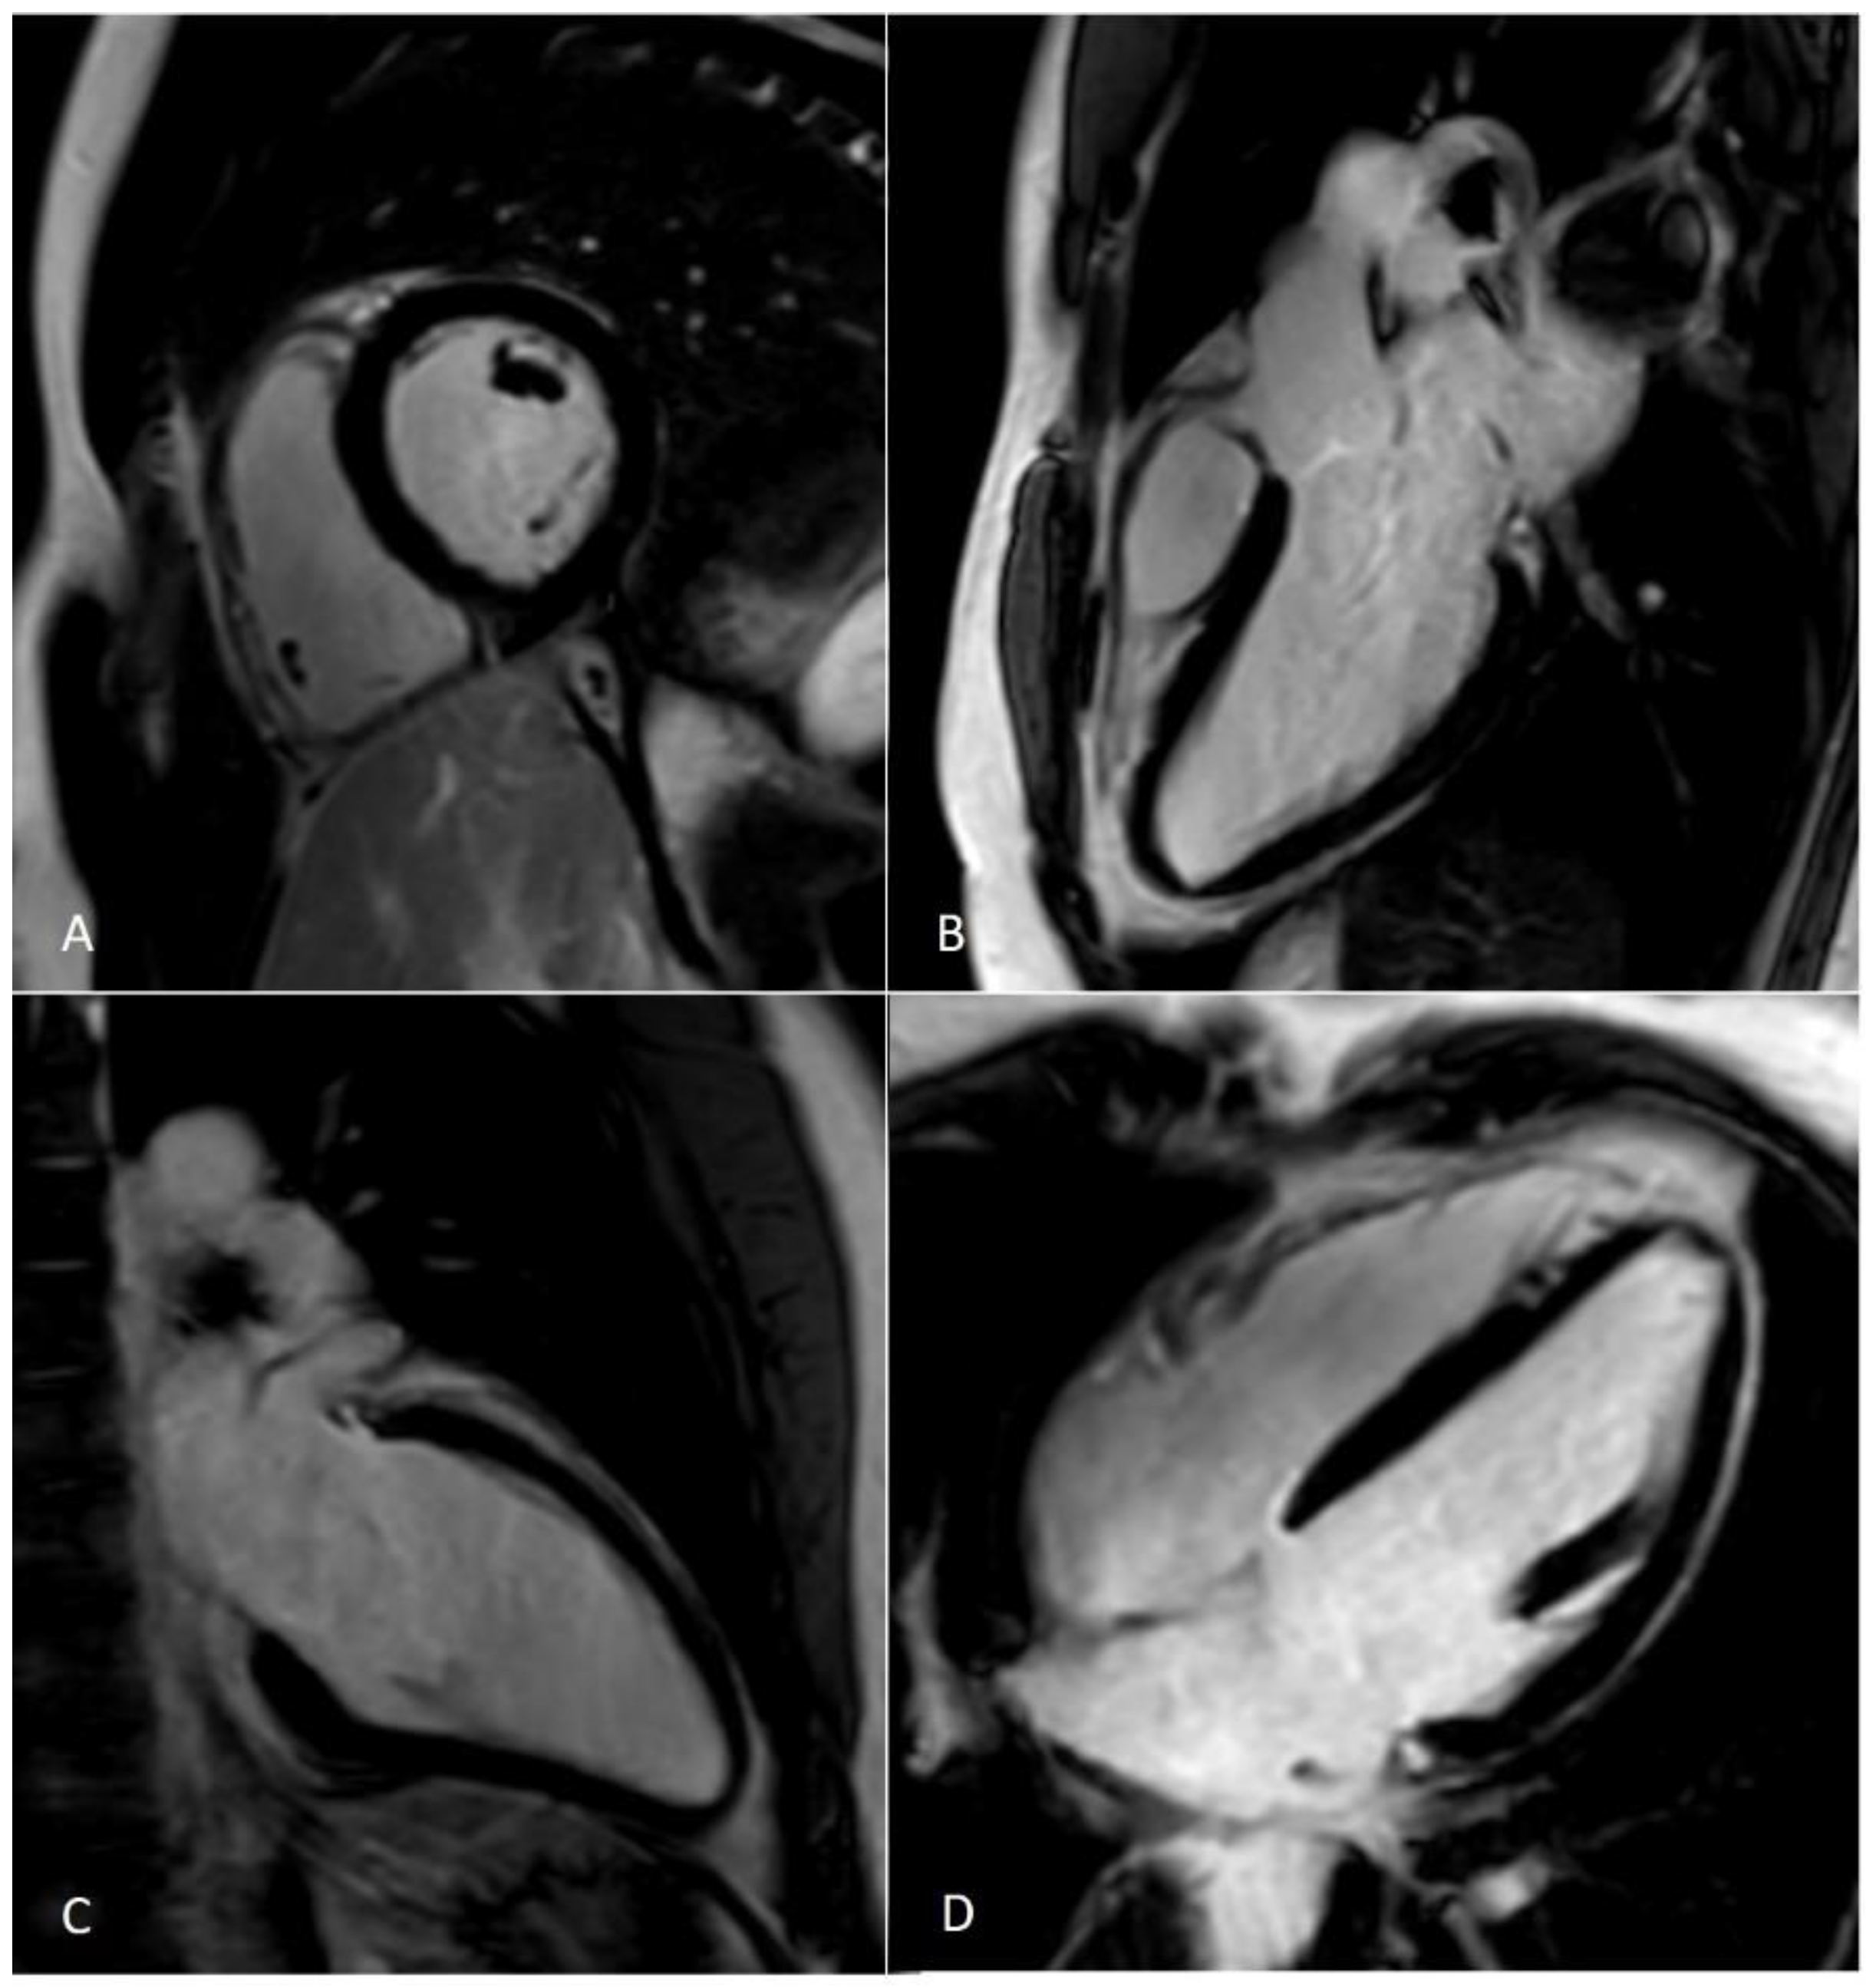

Figure 6.

Artifacts reduction with artificial intelligence implementation. Eighty-two-year-old male patient with previous inferior and inferolateral myocardial infarction. Image (A–C) show the reconstruction of 2D-MSLGE with NR 0% (A), NR 25% (B), and NR 50% (C), respectively. The increasing percentage in NR reconstruction yielded a progressive reduction in image noise in 2D-MSLGE starting from NR 0% (C) and moving through NR 25% (D) and NR 50% (E). A breath artifact characterizing the inferior and inferolateral midapical segments was reduced in the reconstruction in which the 100% artificial intelligence algorithm was applied. In fact, a reduction in quantum noise resulted in better contrast resolution. 2D-MSLGE—2D multisegment late gadolinium enhancement; NR—artificial intelligence reconstruction deep learning noise reduction.